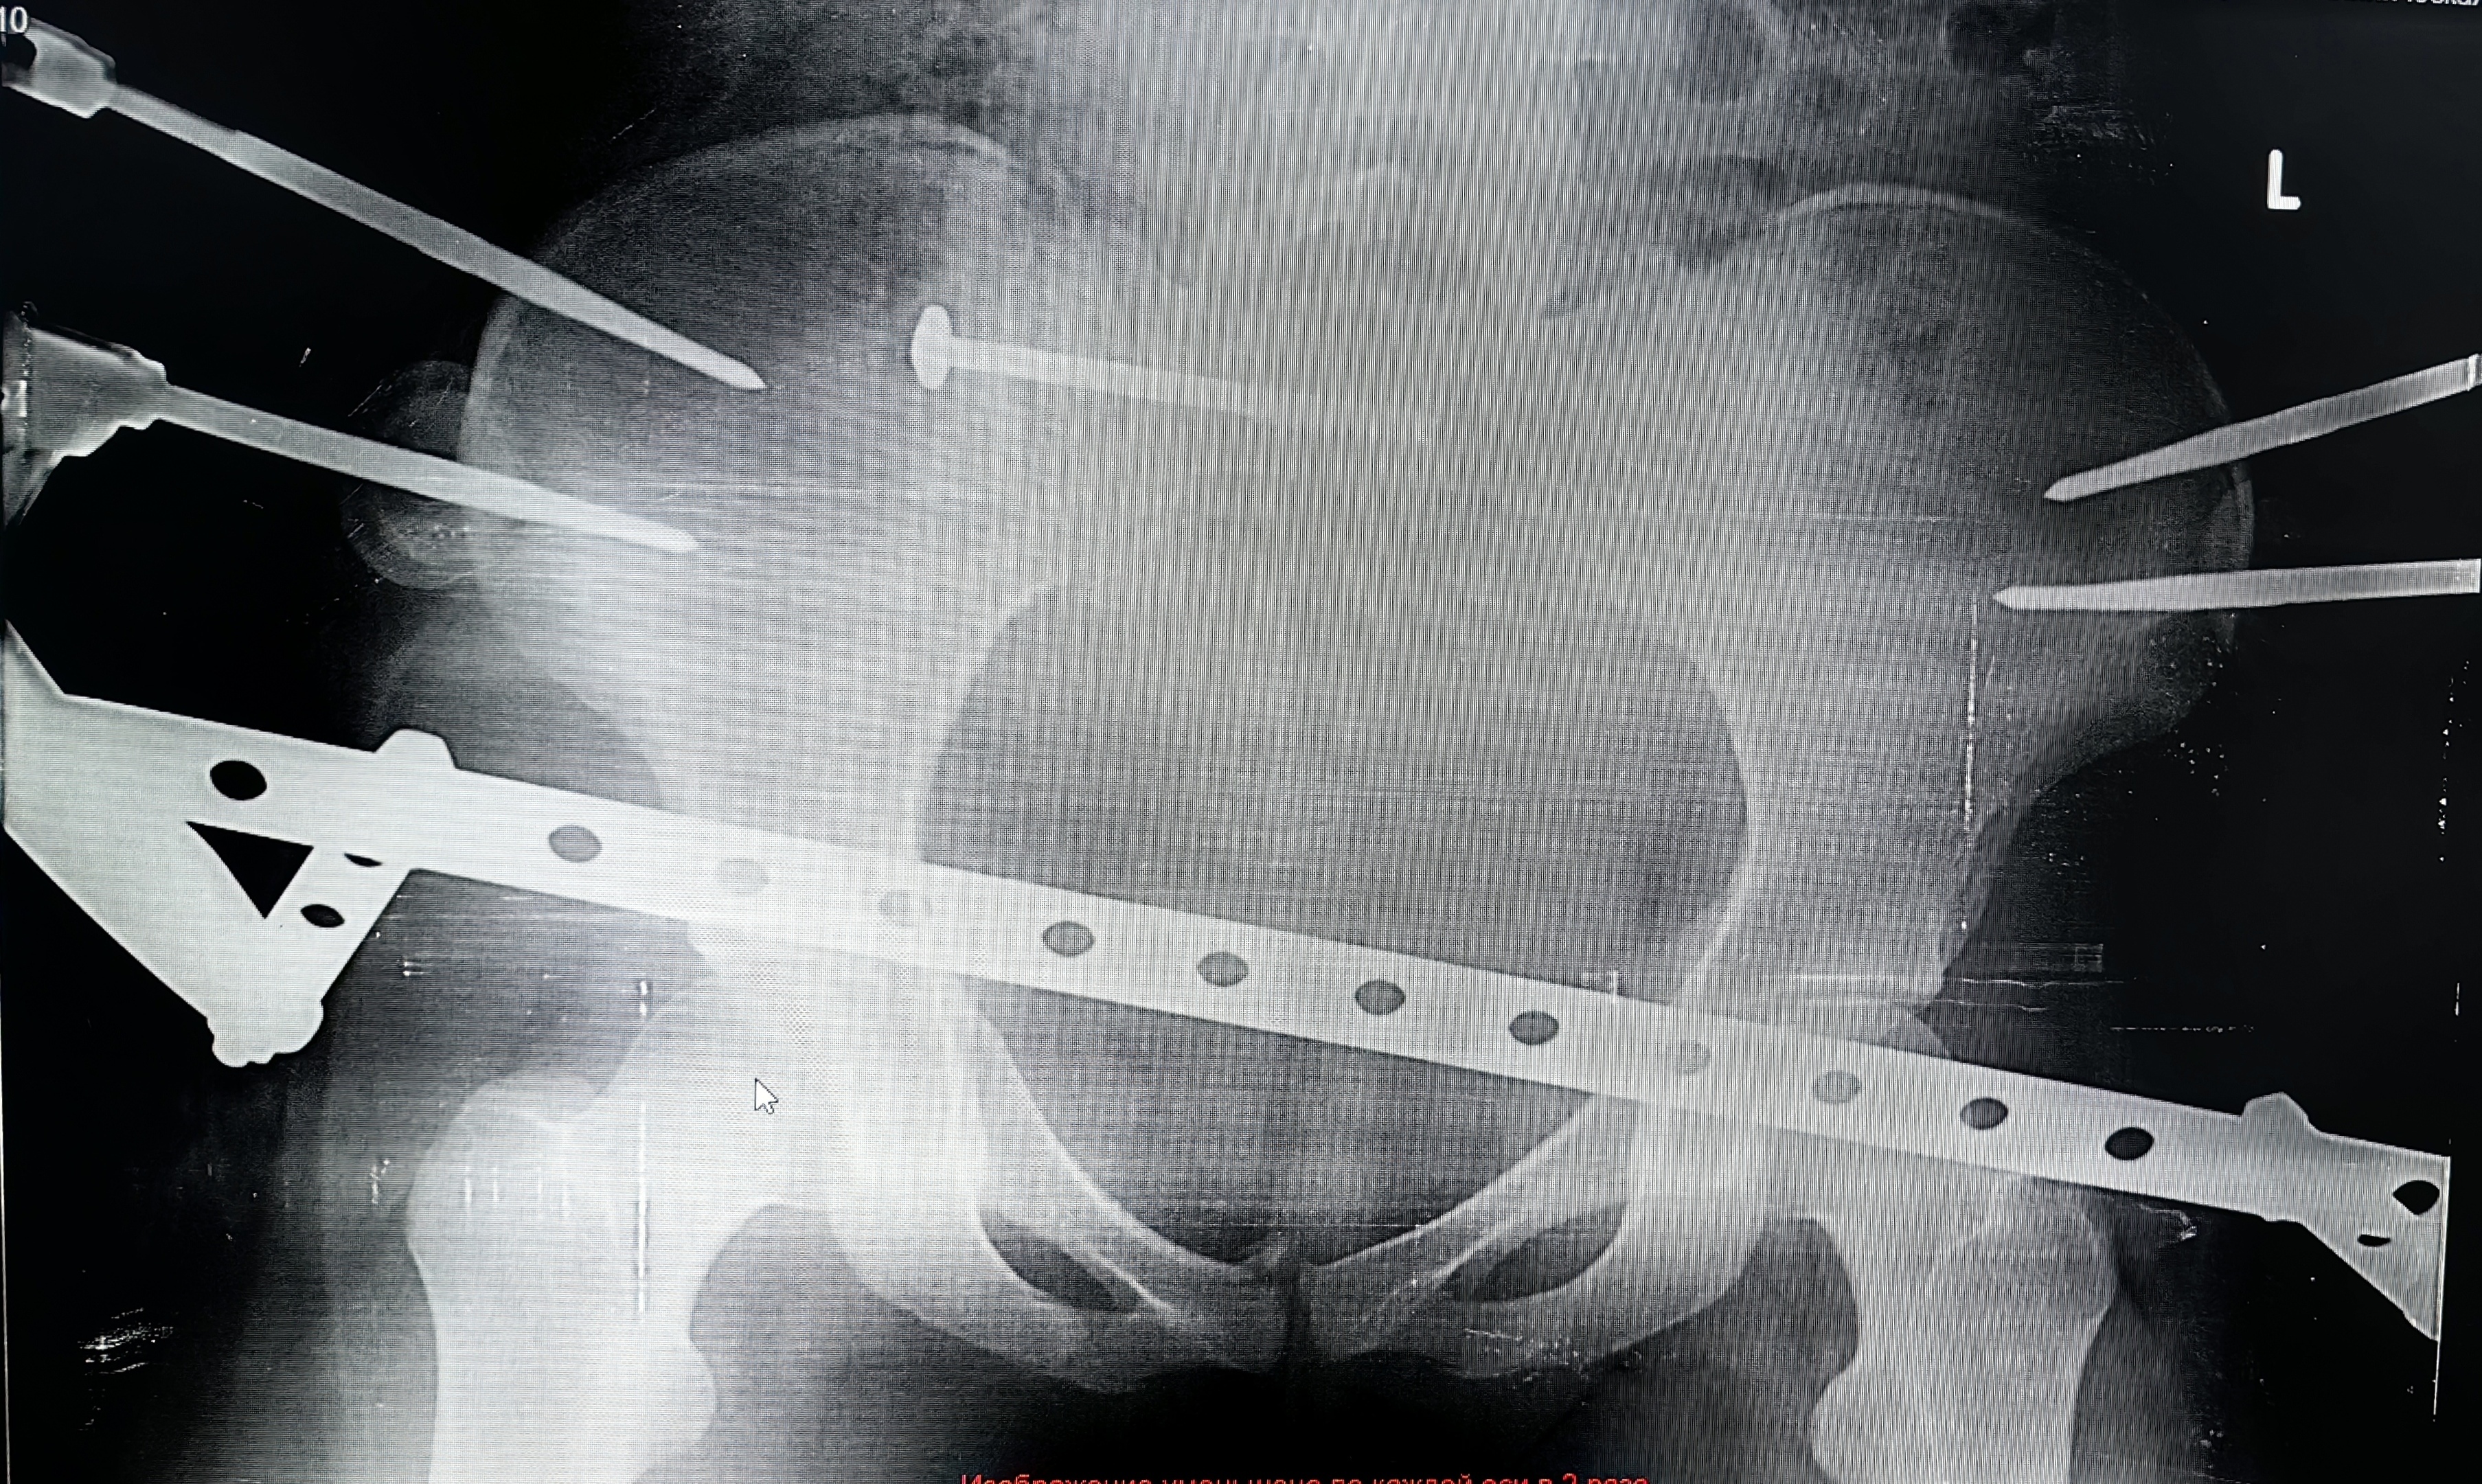

-Хотя по возрастной классификации 17-летние ещё считаются подростками, многие подходы детской травматологии и ортопедии в таком пограничном возрасте уже не эффективны. Поэтому решение приходится искать среди вариантов, применимых ко взрослому населению. В данном случае мы остановились на сложной и довольно редкой операции - малоинвазивном комбинированном остеосинтезе таза. Нам удалось с помощью внешней конструкции и имплантируемых элементов зафиксировать повреждённые крестцовую, лонную и седалищную кости. И при этом обойтись без травматичного доступа. То есть вся операция была выполнена без разрезов, - объясняет заведующий отделением травматологии и ортопедии №1 Сергей Глиняный.

Основные риски были связаны с установкой илеосакрального блокирующего винта в области крестца, где проходят нервы, спинной мозг и множество сосудов. Критически важно не задеть эти структуры, поэтому операция требует от врача соответствующего опыта и высокого уровня мастерства.